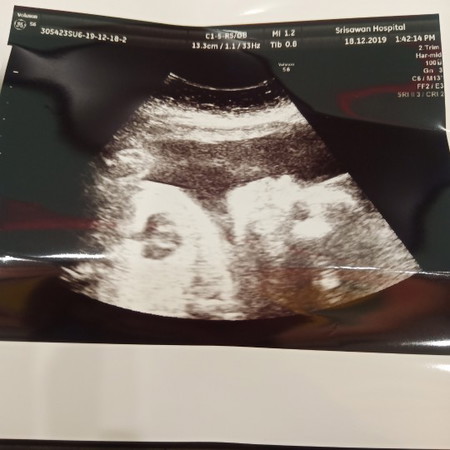

แม่ๆบ้านใหนคลอดเดือนมีนาบ้างค่ะ กี่วีคกันแล้วค่ะ บ้านนี้ 27w5d กำหนดคลอด 10 มีนาคม